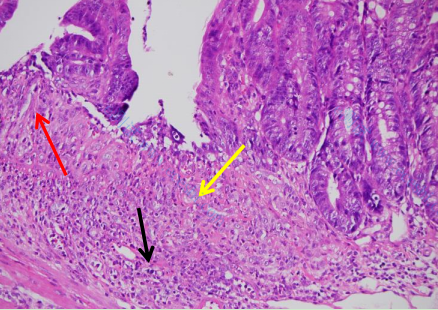

肠组织整体结构异常,组织可见较多粘膜上皮细胞溃疡变性坏死,如图黄色箭头所示,组织坏死处可见少量纤维结缔组织增生,如图红色箭头所示,组织粘膜层杯状细胞数量明显减少,组织可见大量炎症细胞浸润,炎症细胞累积组织全层,如图黑色箭头所示: